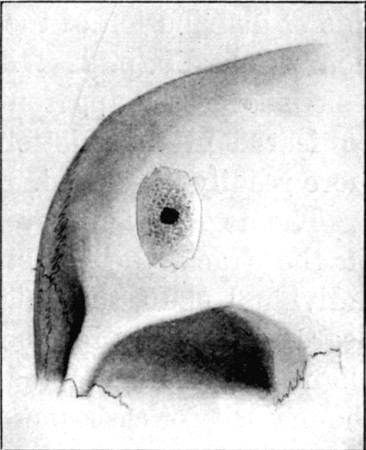

61. Diagram of Aperture of Entry into Cranium 245

62. Aperture of Entry into Frontal Bone 252

63. Fragment of Inner Table Displaced from Opening seen in Fig. 62 253